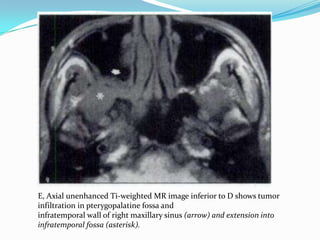

E, Axial unenhanced Ti-weighted MR image inferior to D shows tumor

infiltration in pterygopalatine fossa and

infratemporal wall of right maxillary sinus (arrow) and extension into

infratemporal fossa (asterisk).